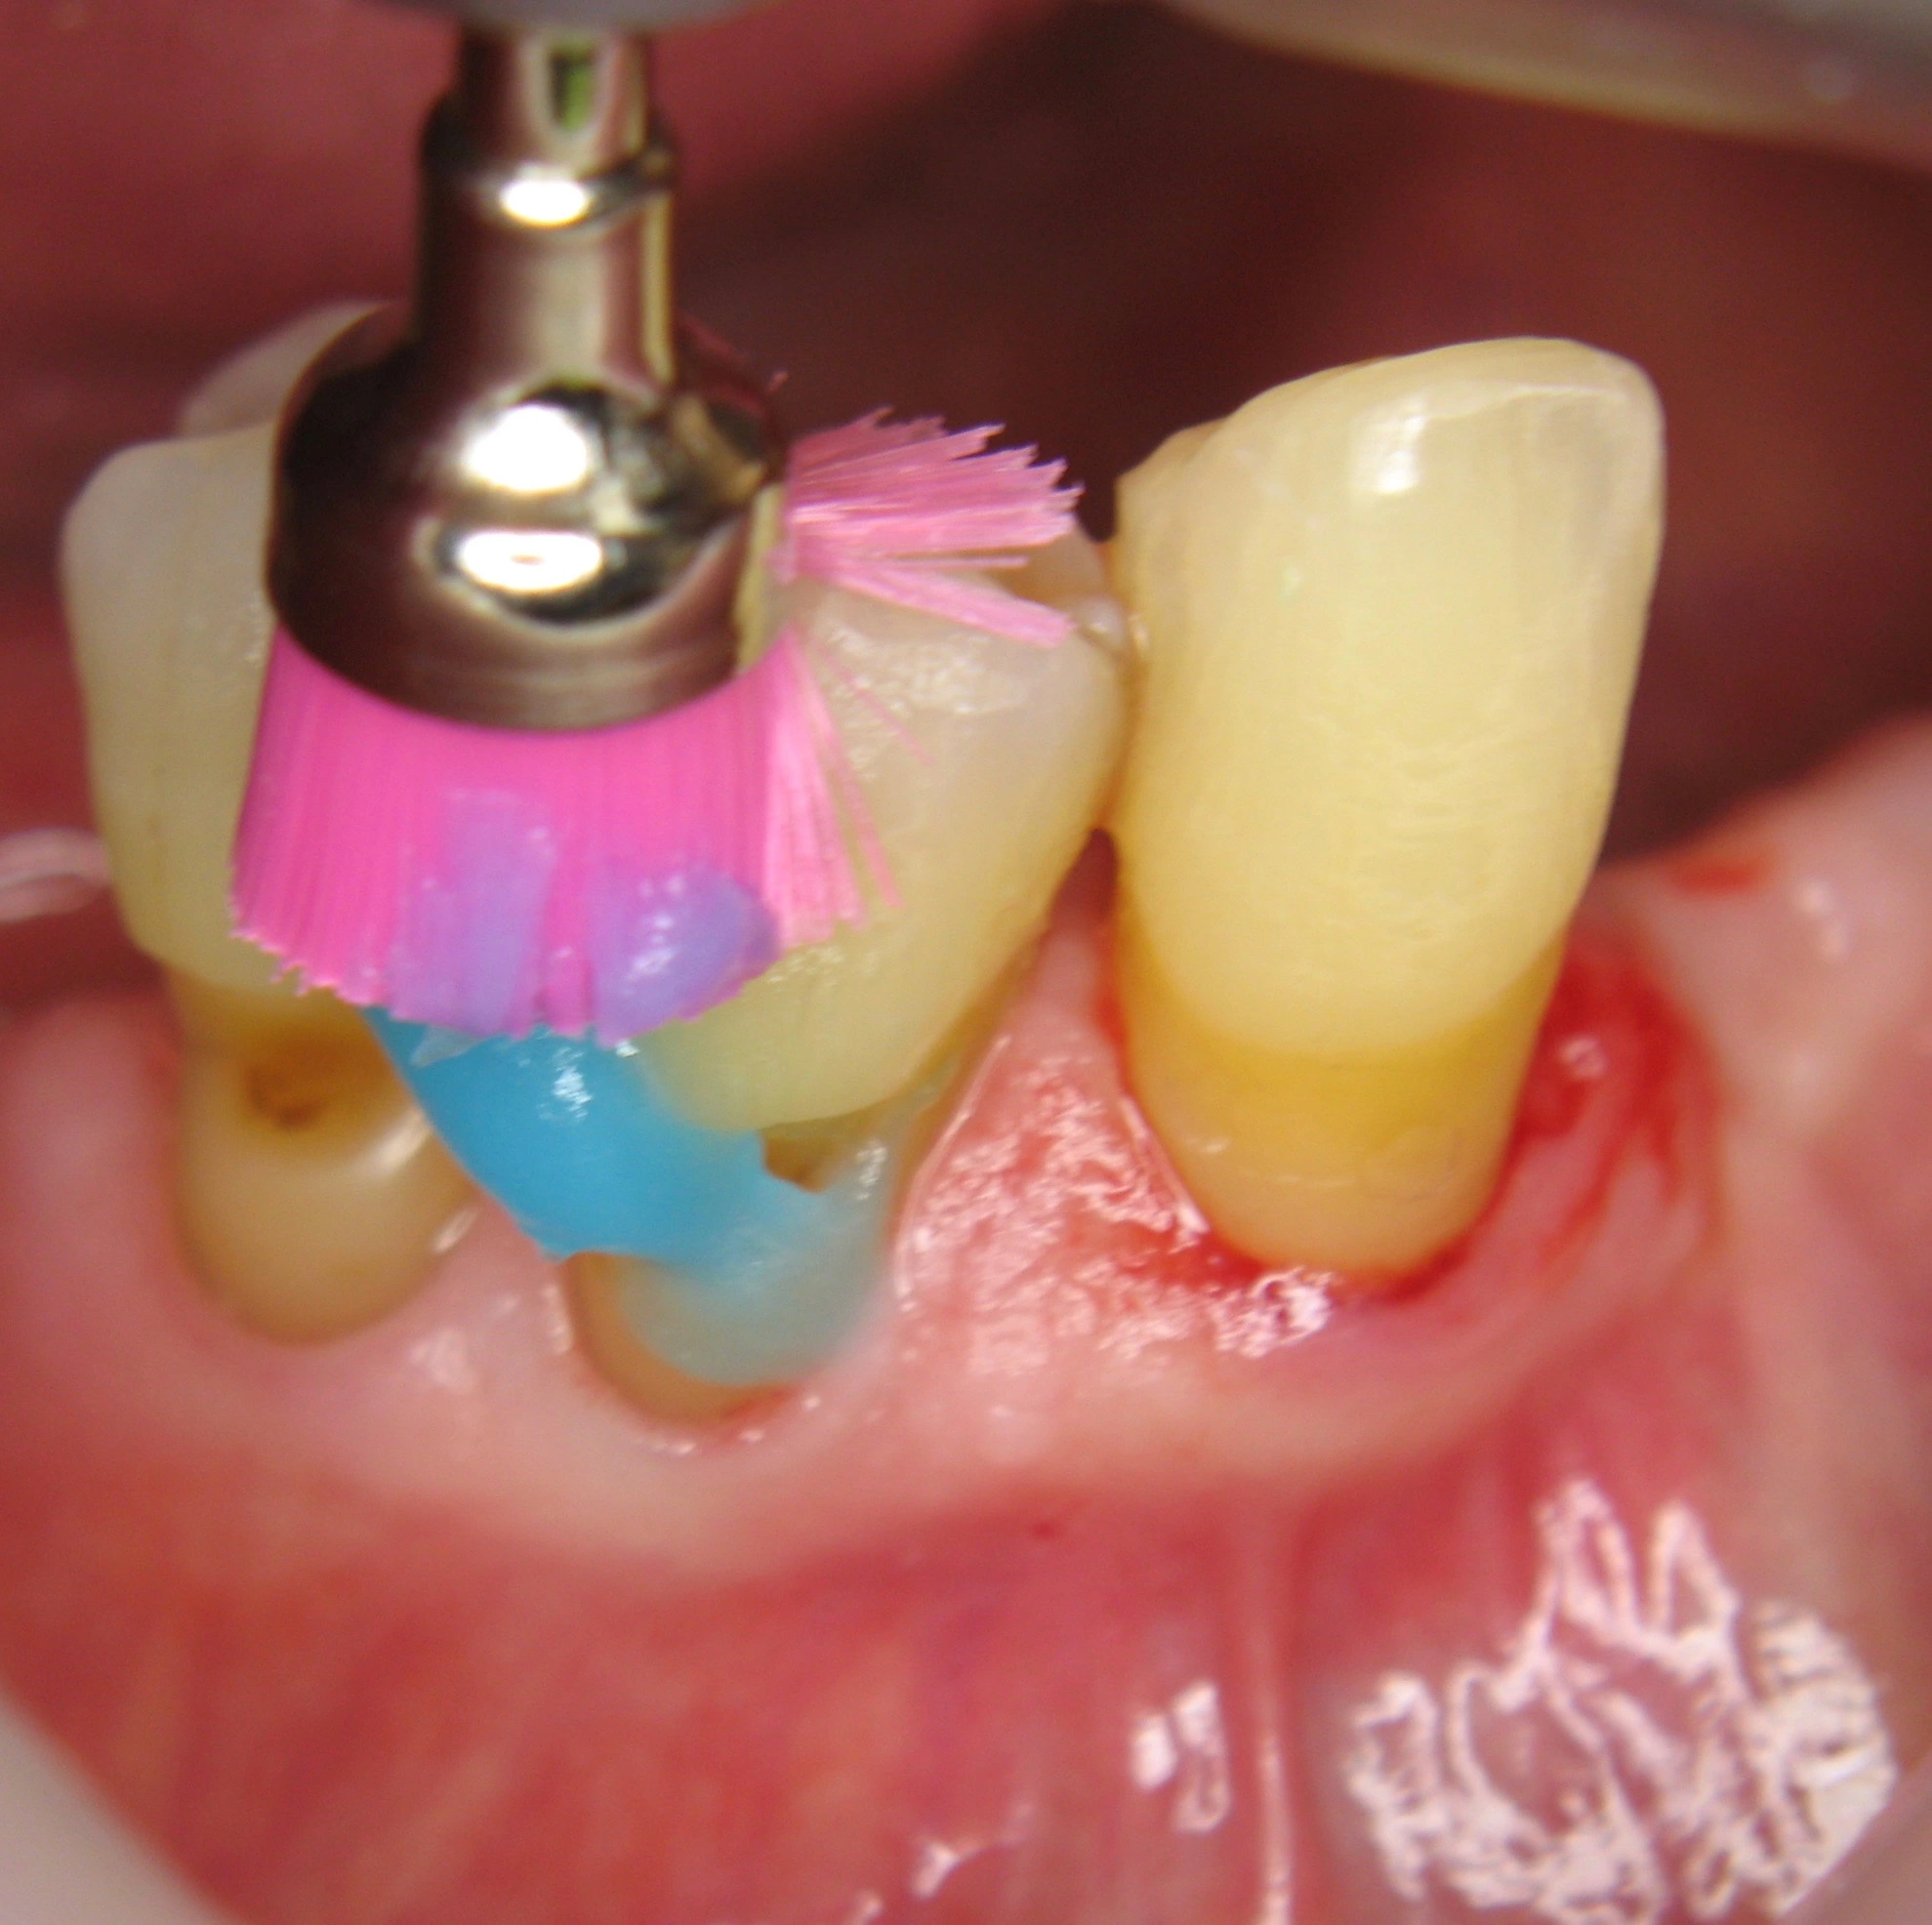

Unsere Therapie in der Praxis sieht eine dreimal jährliche UPT vor, bei der regelmäßig im Bereich der freiliegenden Zahnhälse mit Duraphat® Fluorid 5mg/g Zahnpaste eingebürstet wird (Abb. 3-5). In unserer Mundhygieneinstruktion empfahlen wir dem Patienten, eine Zahnbürste mit weichem Borstenfeld oder alternativ eine elektrische Zahnbürste mit Drucksensor zu nutzen, um zu stark abrasives Putzen zu verhindern. In der Ernährung sollte der Patient auf möglichst weiche und cremige Kost achten und die Trinkmenge erhöhen, um die Schleimhäute regelmäßig zu befeuchten. Zur Verringerung der Mundtrockenheit eignen sich auch speichelanregende Nahrungsergänzungsmittel oder saure, zuckerfreie Bonbons.